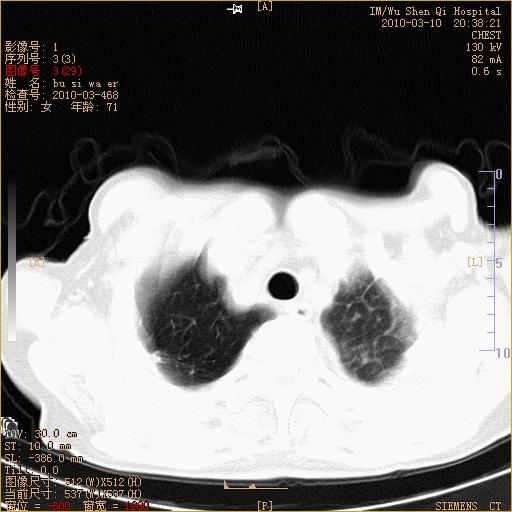

以下是引用随光逐影在2010-3-11 0:41:00的发言:[br]1)考虑左肺及右肺上叶继发性肺结核并左肺炎症感染。2)左侧支气管内膜结核可能;建议必要时行纤支镜检查。3)肺气肿。4)心包膜增厚(或少量心包积液)。5)左侧胸腔积液。